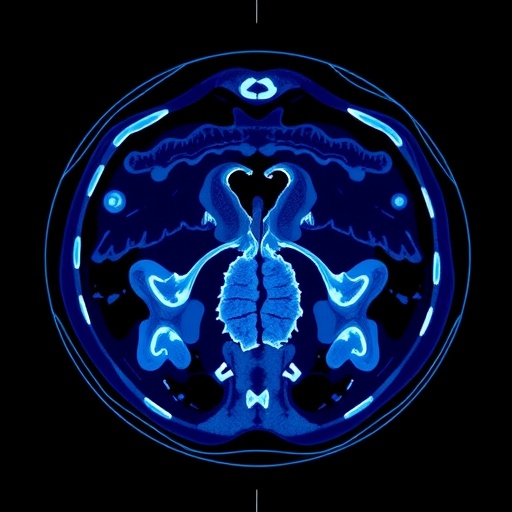

Ovarian cancer remains one of the most challenging cancers to treat, often diagnosed at an advanced stage, which complicates treatment options and patient prognosis. Traditional monitoring techniques and clinical assessments frequently fall short of providing clinicians with robust tools to customize therapy effectively. The researchers utilized computational algorithms that analyze the texture and shape of tumors visible in CT scans to uncover hidden patterns associated with the biological behavior of these malignancies.

The significance of this research cannot be overstated. By integrating radiomics into clinical practice, the authors aim to address a critical gap in current oncology protocols. Radiomics is a field that involves the extraction of a large number of quantitative features from medical images, converting visual information into data that can be analyzed algorithmically. In the case of ovarian cancer, this method could help predict how well a patient might respond to neoadjuvant chemotherapy.

The methodology applied in this multi-center study is noteworthy. Patients were selected from multiple sites, affording a wider demographic representation and enhancing the reliability of the findings. The researchers collected CT images from these patients before chemotherapy treatment, followed by a detailed analysis of the imaging data to extract relevant features using advanced algorithms. This innovative approach resulted in the creation of a radiomic signature, which serves as a predictive tool for clinicians.